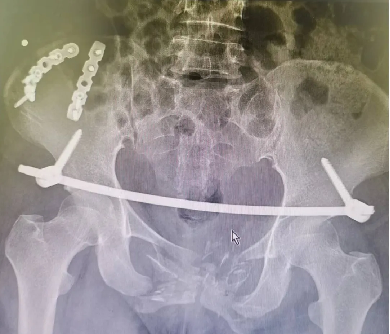

創傷性骨盆骨折致尿道斷裂患者,膀胱(guāng)造瘺術後,需穩定骨折端(duān)避免二次傷害。

骨盆前環微創經皮內固定技術(INFIX技術)固(gù)定結合了內固定和外固定的優點,揚長(zhǎng)避短,針對此類(lèi)患(huàn)者,有效避免了術後深部感染,又避(bì)免(miǎn)了使(shǐ)用外固(gù)定的手術並發症,讓患者在最佳(jiā)治療時機獲得了骨盆環的穩定,並能早期開始功能鍛煉,最大程度上降低了因傷致殘的機(jī)率。